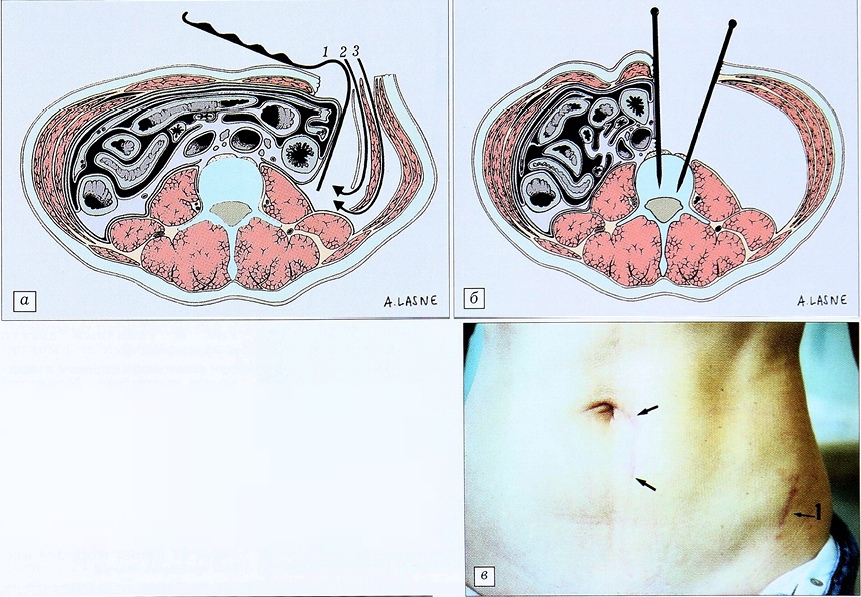

Для достижения уровня L4-5 (рис. 2) возможны два стратегических варианта. Диссекцию можно начать, как для подхода к нижележащим уровням, используя ретроперитонеальную фасцию для того, чтобы убедиться в расслоении париетальной брюшины. Этот же разрез позволяет осуществить доступ к L3, затем к L4 и L5, при этом мочеточник остается плотно прилегающим к перитонеальной сумке. Если удается достичь уровня L4-5 под прямым углом, диссекция должна выполняться с особой осторожностью, поскольку в некоторых случаях мочеточник прилегает к брюшине неплотно и может располагаться близко к m. psoas и подвздошным сосудам. У некоторых пациентов fascia iliaca плотная и тесно прилегает к предвертебральным сосудам. В этих случаях ее следует рассекать вперед на уровне m. iliopsoas, чтобы войти непосредственно в предвертебральное пространство. У большинства же больных, особенно пожилого возраста, эти ткани хрупкие и достаточно произвести простое расслоение предвертебральной фасции.

Рис. 2. Доступ к уровню L4-5. a — возможен доступ подбрюшинный (1), либо под поперечной фасцией (2), либо между косой внутренней мышцей и поперечной мышцей (3); б — выполненный доступ с установленными спицами для смещения мягких тканей; в — рубец после разреза кожи (1 — разрез в месте забора костного трансплантата).

Систематически осуществляется превентивный гемостаз в предвертебральной области во избежание кровотечения из поперечных поясничных сосудов. Мы практически никогда не используем скобки из-за возможности их смещения в дальнейшем. Коагуляция сегментарных сосудов выполняется без их пересечения. Нужно помнить о потенциальной опасности повреждения симпатического ствола, хотя он и находится латеральнее. Спицы следует проводить только в передний кортикальный слой тела позвонка, поскольку эта зона отличается повышенной кровоточивостью. Обычно их располагают по средней линии, но иногда и на боковой поверхности тела позвонка — чтобы «освободить» ассистента, а также обойтись без применения бокового ретрактора. Располагая эти спицы веерообразно, мы получаем очень хороший обзор позвоночника. Для промежуточных уровней — L2-3 и L3~4 (рис. 3) медиальный ретрактор не требуется, что облегчает рентгенологический контроль во время операции. На уровнях L4-5 и L5-S1 дистальный ретрактор может быть оставлен на месте для защиты подвздошных сосудов и особенно общей подвздошной вены.